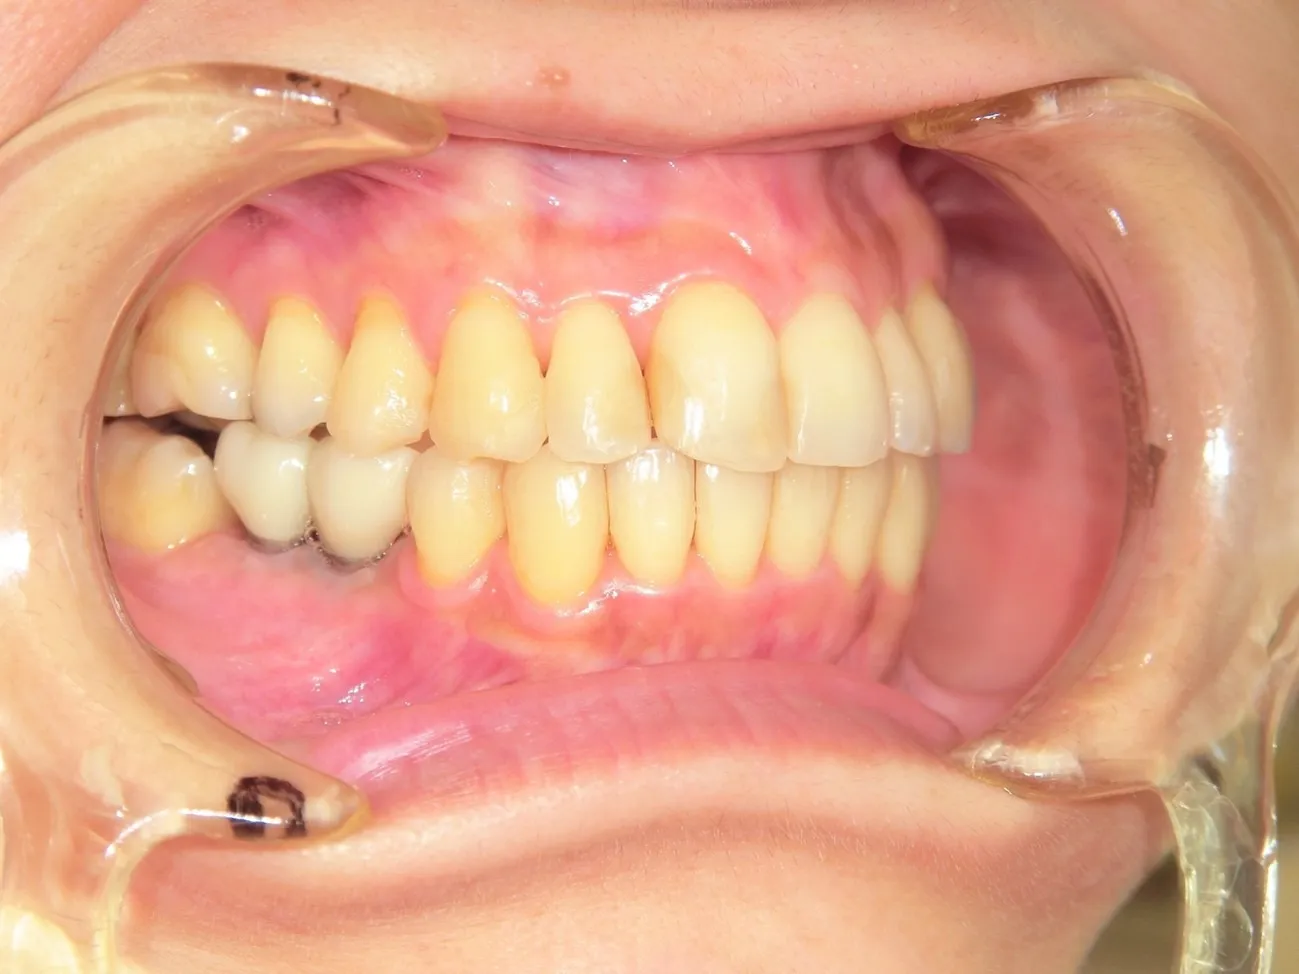

施術を検討されている方に様々なケースの施術前後の違いをご確認いただけるよう、インプラントやインビザラインでの矯正の症例を画像も用いて一覧にして載せております。「ずれている前歯を揃えたい」「受け口を直したい」「抜けた歯をキレイに整えたい」など、様々なご相談を承り、ご予算や仕上がりのご要望はもちろんのこと、長期的な口腔の健康維持も考慮したプランをご提案いたします。